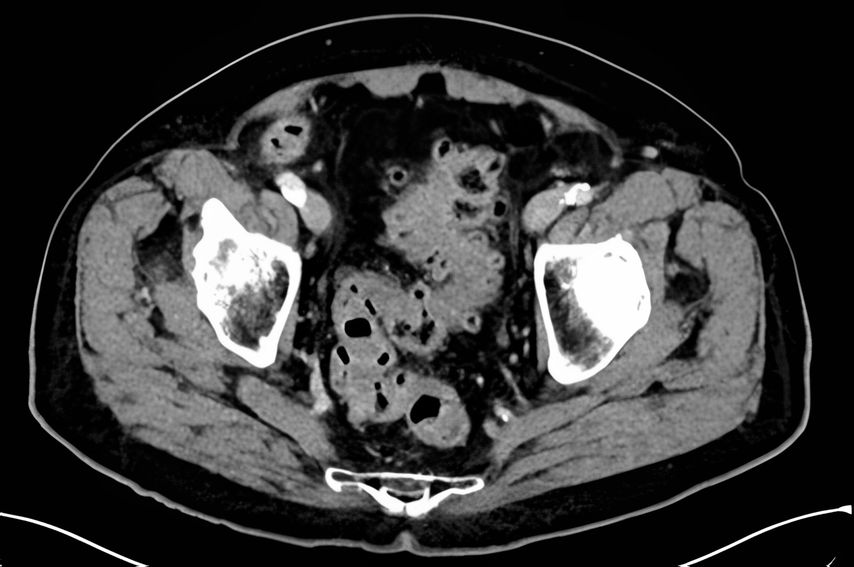

Zusammenfassend haben wir in dieser Arbeit das breite Spektrum, welches die Divertikulitis als Erkrankung einnehmen kann, von milden unkomplizierten Verläufen bis hin zu lebensbedrohlichen Komplikationen, dargestellt (Abb. 3). Die Therapie ist stadienabhängig und umfasst die symptomatische Behandlung bis zur Notfalloperation. Eine präzise Diagnostik, Stadieneinteilung und daran ausgerichtete Wahl der Therapie ist die Grundvoraussetzung, um eine optimale Patientenversorgung zu gewährleisten und dem Patientenwohl gerecht zu werden. Die chirurgische Therapie ist deutlich zurückhaltender geworden, jedoch ist die Datenlage ausreichend, um Patienten, die nach mehreren Schüben in ihrer Lebensqualität eingeschränkt sind, die Operation zu empfehlen.